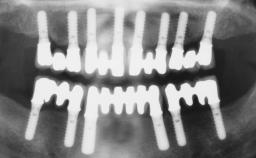

| Timing of placement | Immediate Placement (extraction sockets) (Type I) |

| Loading Protocol | Immediate |